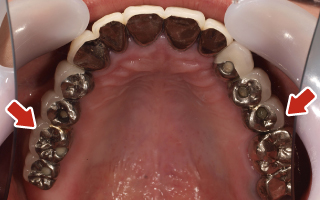

Before

After

| 55歳 男性 | |

|---|---|

| 主訴 | 前歯でしか咬めなく、食事を摂るのに非常に困難で辛い |

| 処置内容 | 上顎6本、下顎3本 |

| 治療費用 | 上顎: 約230万(税込) 下顎: 約120万(税込) |

| 治療期間 | 上顎: 1年(仮歯まで8ヶ月) 下顎: 8ヶ月(仮歯まで5ヶ月) |

| リスク | 上部構造物、仮歯の破折、術後の腫れ(3日)、人工歯根脱落リスクがあります |